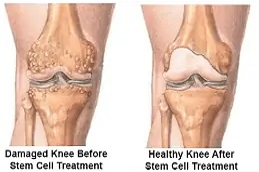

يُعد علاج البلازما الغنية بالصفائح الدموية للركبة، المعروف أيضًا بحقن البلازما للمفاصل، من الأساليب الرائدة في مجال الطب التجديدي، ويُستخدم هذا العلاج بشكل فعّال في حالات آلام الركبة وتلف المفاصل، حيث يعتمد على استخلاص مكونات البلازما من دم المريض نفسه، ثم إعادة حقنها في المنطقة المصابة، يهدف هذا الإجراء إلى تحفيز عملية الشفاء الطبيعي في الجسم، وتسريع تجدد الأنسجة، مع تقليل الالتهاب وتخفيف الألم بشكل ملحوظ.

تُعد حقن البلازما الغنية بالصفائح الدموية (PRP) أحد الأساليب المستخدمة في علاج الركبة، حيث يُؤخذ مقدار صغير من دم المريض ويُعالج باستخدام جهاز الطرد المركزي لفصل مكونات الدم، واستخلاص البلازما والصفائح الدموية، بعد ذلك يُعاد حقن هذا التركيز مباشرة في الركبة أو المفصل المتضرر للمساعدة في تعزيز الشفاء.

| خشونة المفاصل (الفُصال العظمي): | يمكن لعلاج PRP أن يخفف الألم ويحسن وظيفة المفصل لدى مرضى خشونة الركبة عن طريق تحفيز تجديد الأنسجة وتقليل الالتهاب. |

| إصابات الغضروف الهلالي: | يمكن استخدام PRP لعلاج تمزقات الغضروف الهلالي، وهو الجزء الذي يعمل كوسادة تساعد على امتصاص الصدمات داخل مفصل الركبة. |